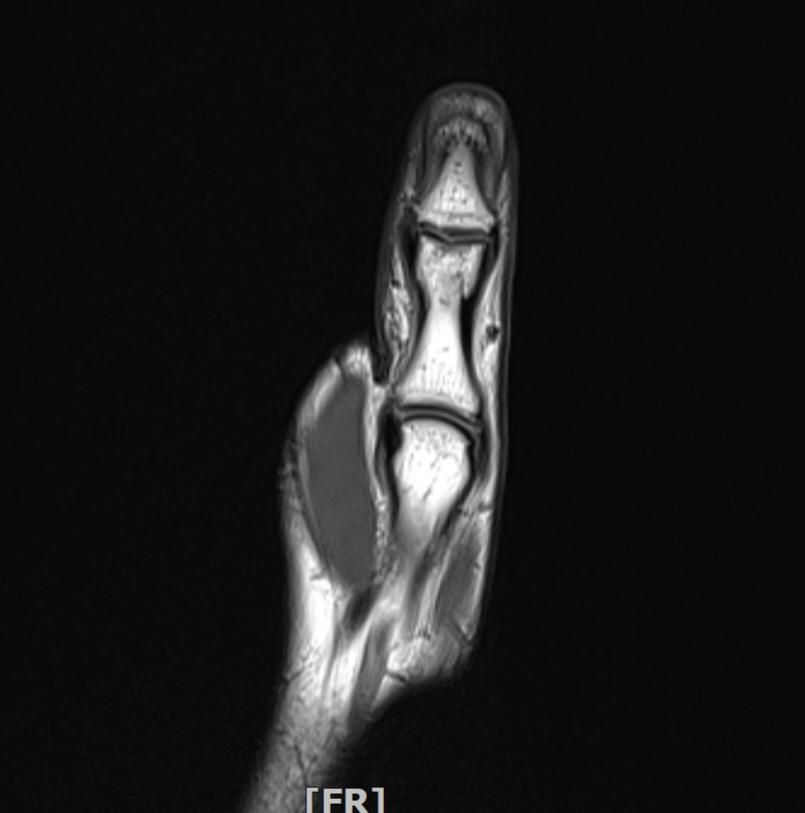

왼손 엄지손가락 부상 mri판독부탁드립니다

임팩에 장갑이 말리면서 엄지도 같이 말렸습니다

현재 손이 가끔 욱씬거리고 평소보다 뻣뻣하며 불안정감이 있는듯 합니다. mri사진으로 판독 가능하실까요 감사합니다.

• 2번 째 사진

정확한 판독을 하긴 어렵지만 연부조직의 주변부의 염증이 보여집니다.

올려주신 사진 상에서는 특별하게 큰 문제가 없을 수 있으나 부상과정에서 인대나 힘줄에 발생했던 부상으로 인해 긴장감이나 움직임 제한, 통증이 나티나는 경우에는 치료를 받아보시는 것도 좋겠습니다.

Mri 판독은 영상 전문의가 직접 이미지를 확인해야 정확하지만 엄지 부상 후 욱씬거림과 뻣뻣함, 불안정감은 인대 손상이나 골절, 건초염 가능성을 시사합니다. Mri에서는 인대 파열, 연골 손상, 골수 부종 등을 중점적으로 평가합니다. 증상이 지속되면 정형외과 전문의에게 영상 판독과 임상 진단을 반드시 받는 것이 안전합니다!